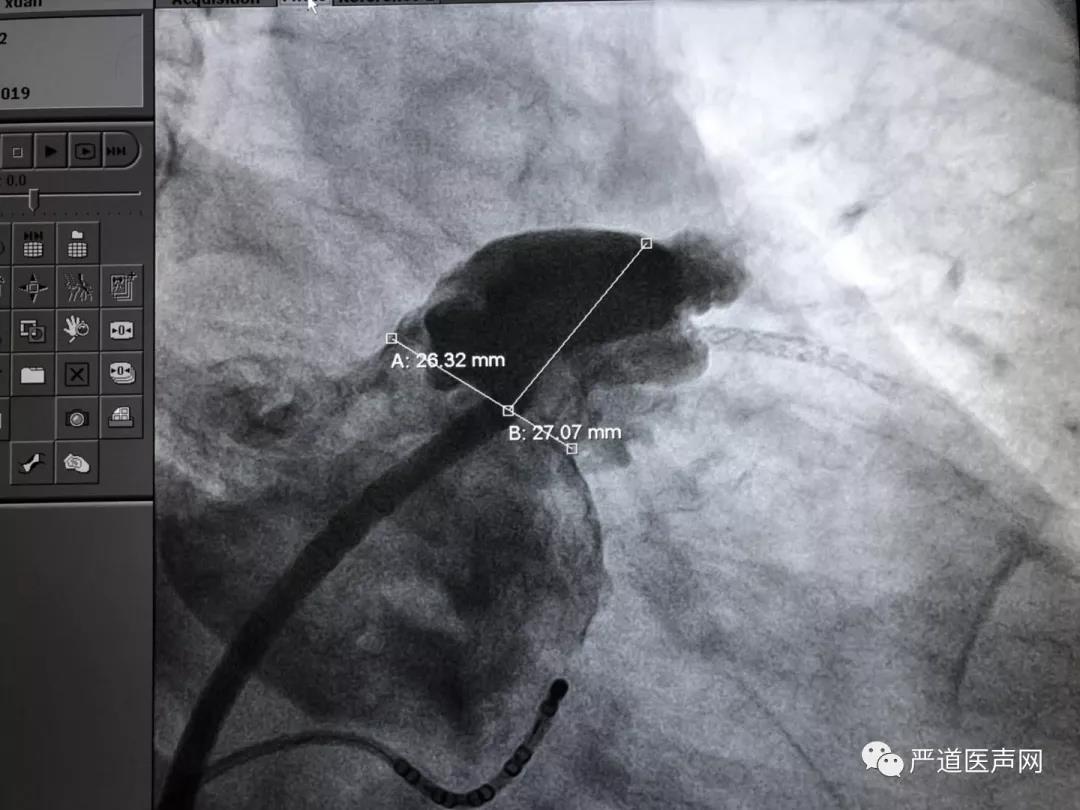

左心耳肝位造影

封堵伞展开后造影